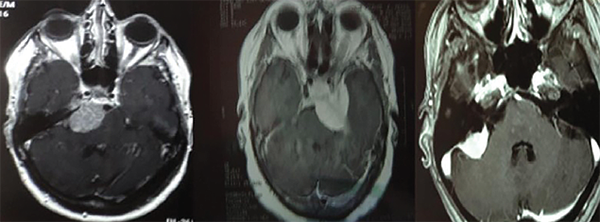

Por definición, los meningiomas petroclivales tienen su origen medial a los pares craneales V, VII, VIII, IX, X y XI, y pueden alcanzar el tentorio.1,3,5,6 A menudo se extienden hacia la fosa media, el seno cavernoso y la cisterna prepontina (Figura 1). Pueden descender al agujero magno, pudiendo invadir la piamadre y causar compresión del tronco encefálico. En los casos en que hay edema del tronco encefálico (hipodensidad en la tomografía o hiperseñal enT2 en la resonancia magnética) o una forma dentada e irregular del tumor sobre el tejido cerebral, la extracción total es muy difícil o imposible sin causar déficits neurológicos3-5(Figura 2). Los meningiomas del clivus inferior (foramen magno), petrosos, tentoriales y del ala esfenoidal pueden alcanzar estas áreas, pero no se consideran de origen petroclival.6

Figura 1: Resonancia magnética axial en T1 con gadolinio. Meningioma petroclival (izquierda), meningioma esfenopetroclival (centro), meningioma petroso (derecha).